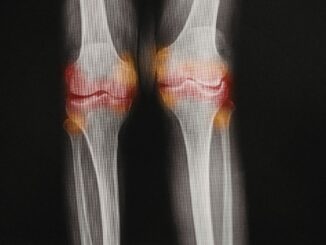

ד"ר אלעד לאור - כאבי מפרקים

איך מתמודדים עם כאבי מפרקים בגיל השלישי?

רבים מאיתנו מתרגלים למחשבה שכאב הוא חלק בלתי נפרד מההתבגרות שלנו. אנחנו מרגישים דקירה בברך כשאנחנו קמים מהכיסא או נוקשות בגב בשעות הבוקר ומניחים ש"ככה […]